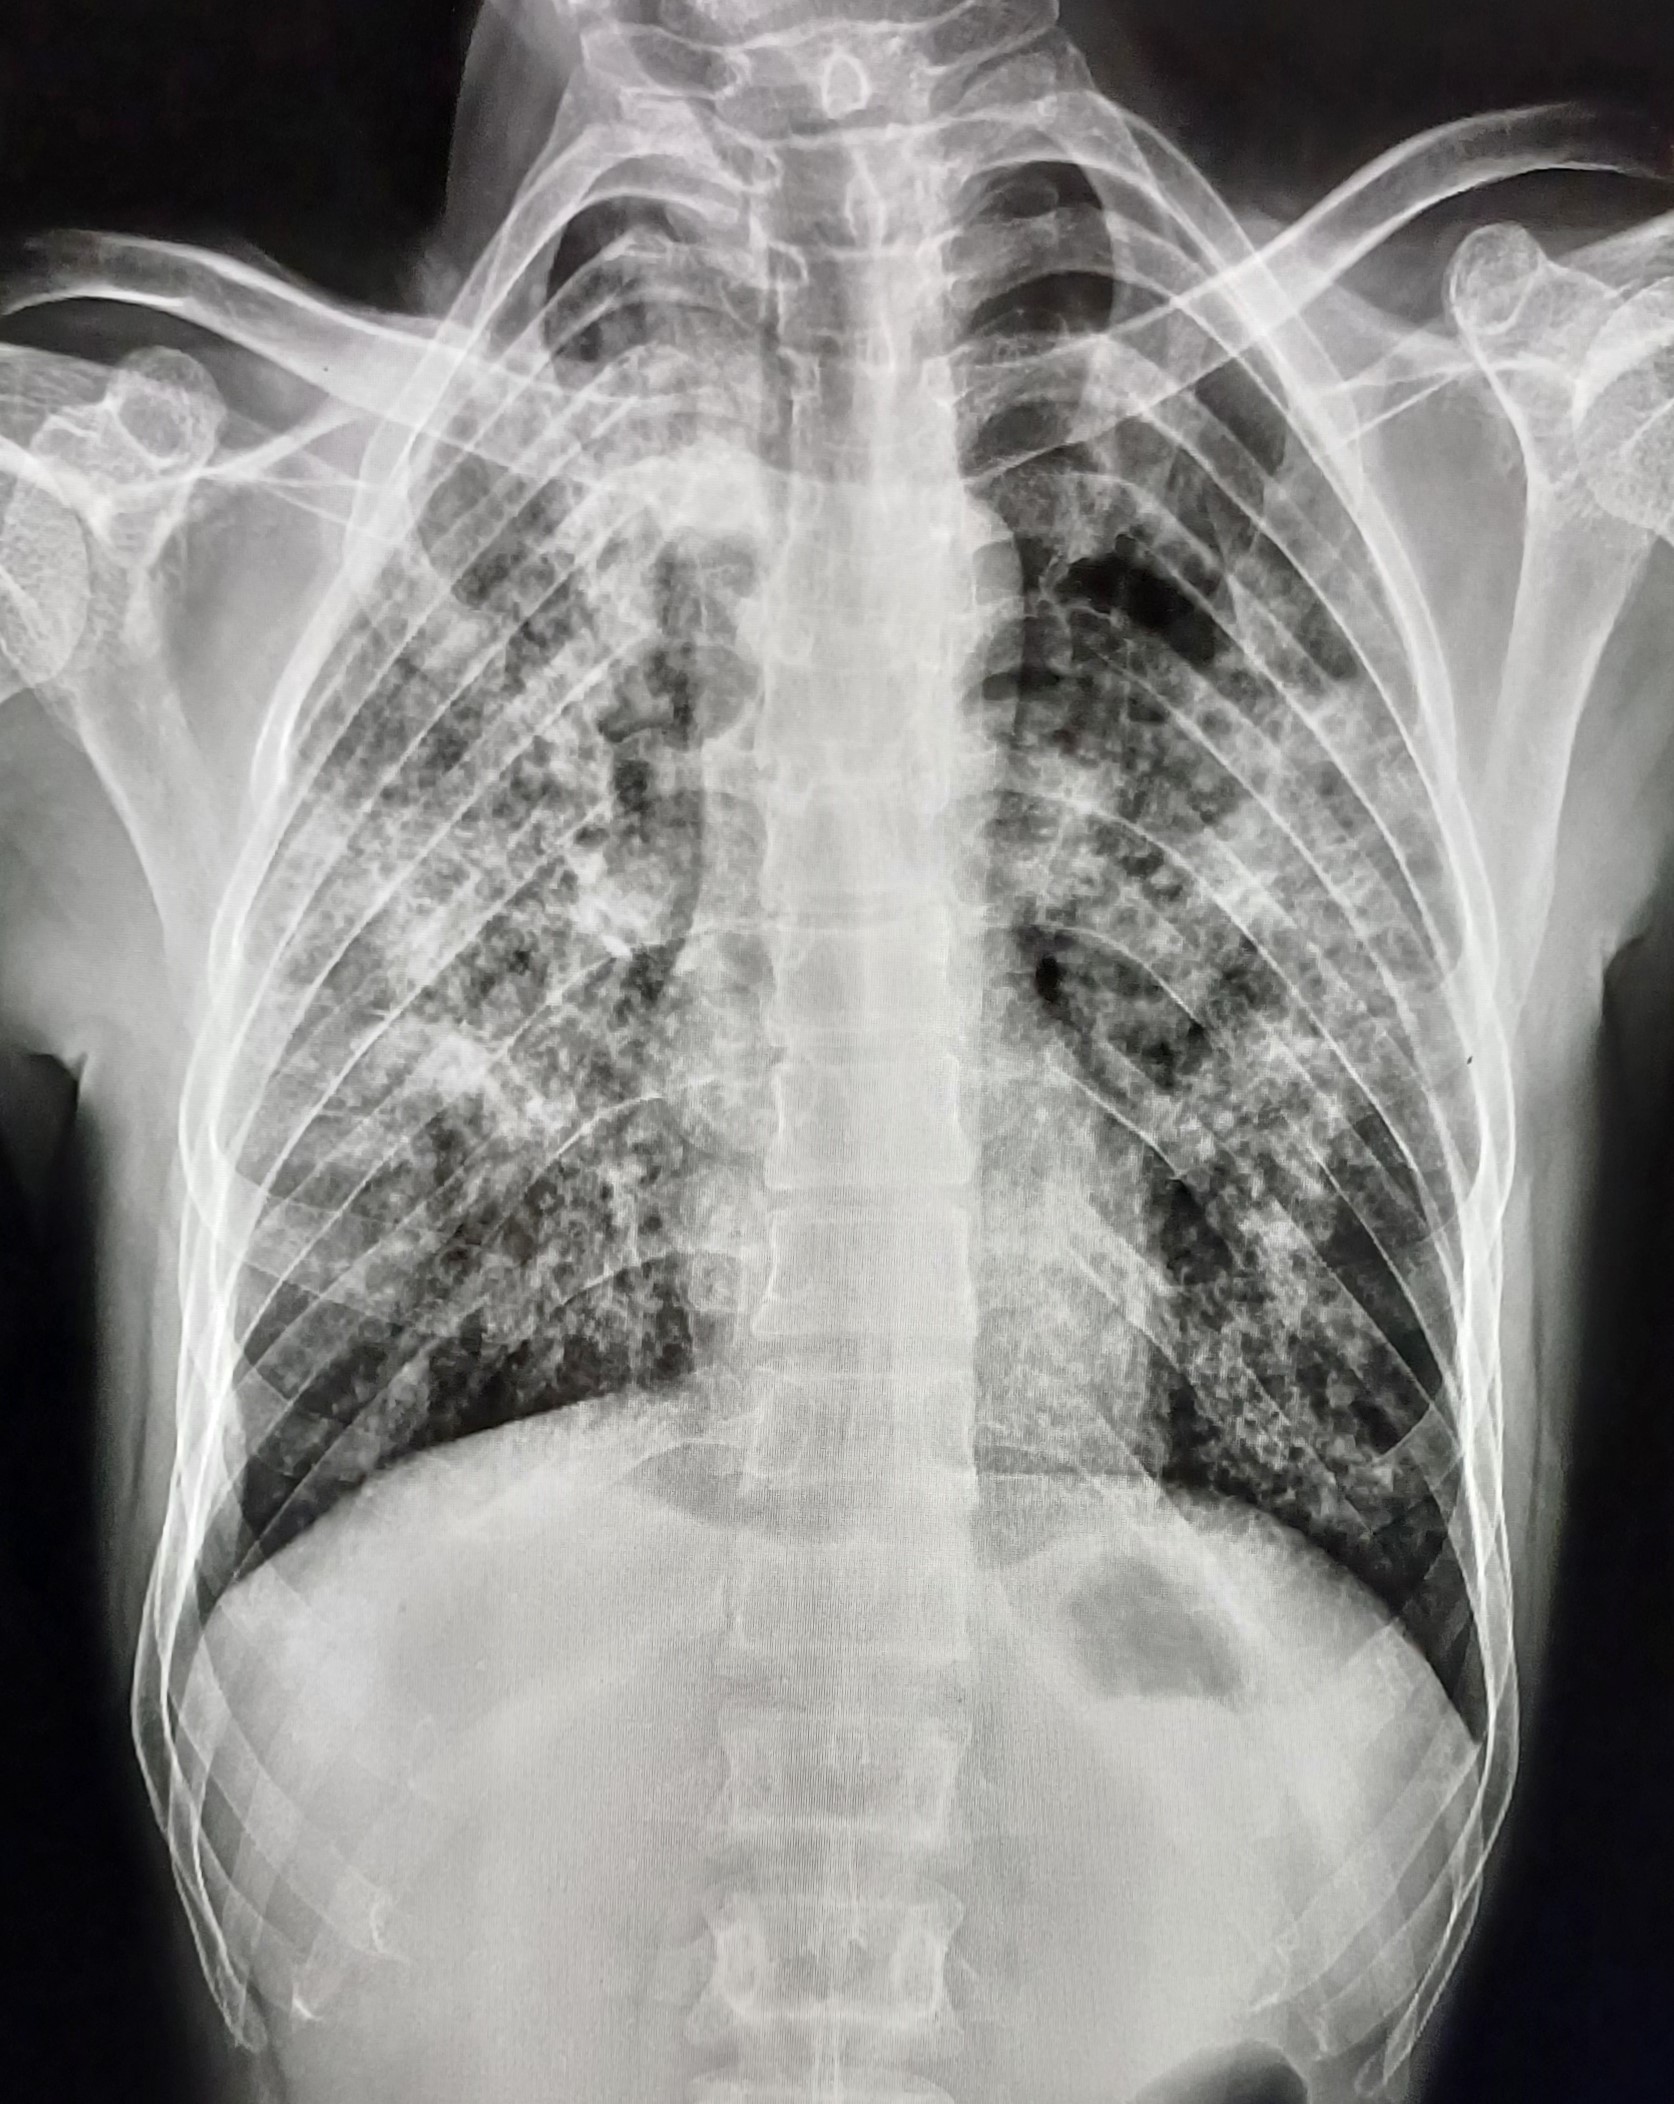

| 4 | IGGMC, Nagpur, Nagpur | P2 | 29-4468 | Moh. Salehuddin | Consent taken on Paper | 68 Yrs. |

Provisional Diag : Miliary TB?

Final Diag : Miliary TB |

TB Case (Confirmed) | Bilateral Infiltrate Query Miliary | Abnormality visible on x-ray |

View |